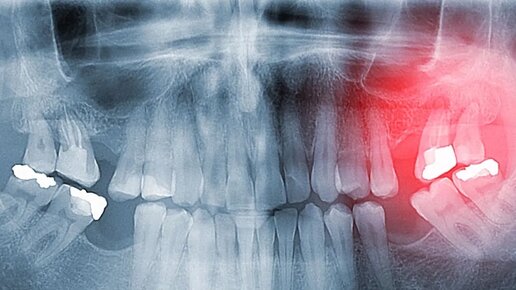

Периодонтит — это серьёзное воспаление, которое нельзя оставлять без внимания

Периодонтит — это серьезное воспалительное заболевание тканей, окружающих корень зуба, которое может привести к серьезным осложнениям, вплоть до потери зуба. Болезнь возникает из-за инфицирования периодонта — структуры, соединяющей зуб с челюстной костью. Без своевременного лечения воспалительный процесс может привести к разрушению костной ткани и распространению инфекции на соседние структуры. Основной причиной периодонтита является проникновение инфекции в периодонтальные ткани. Это может произойти...